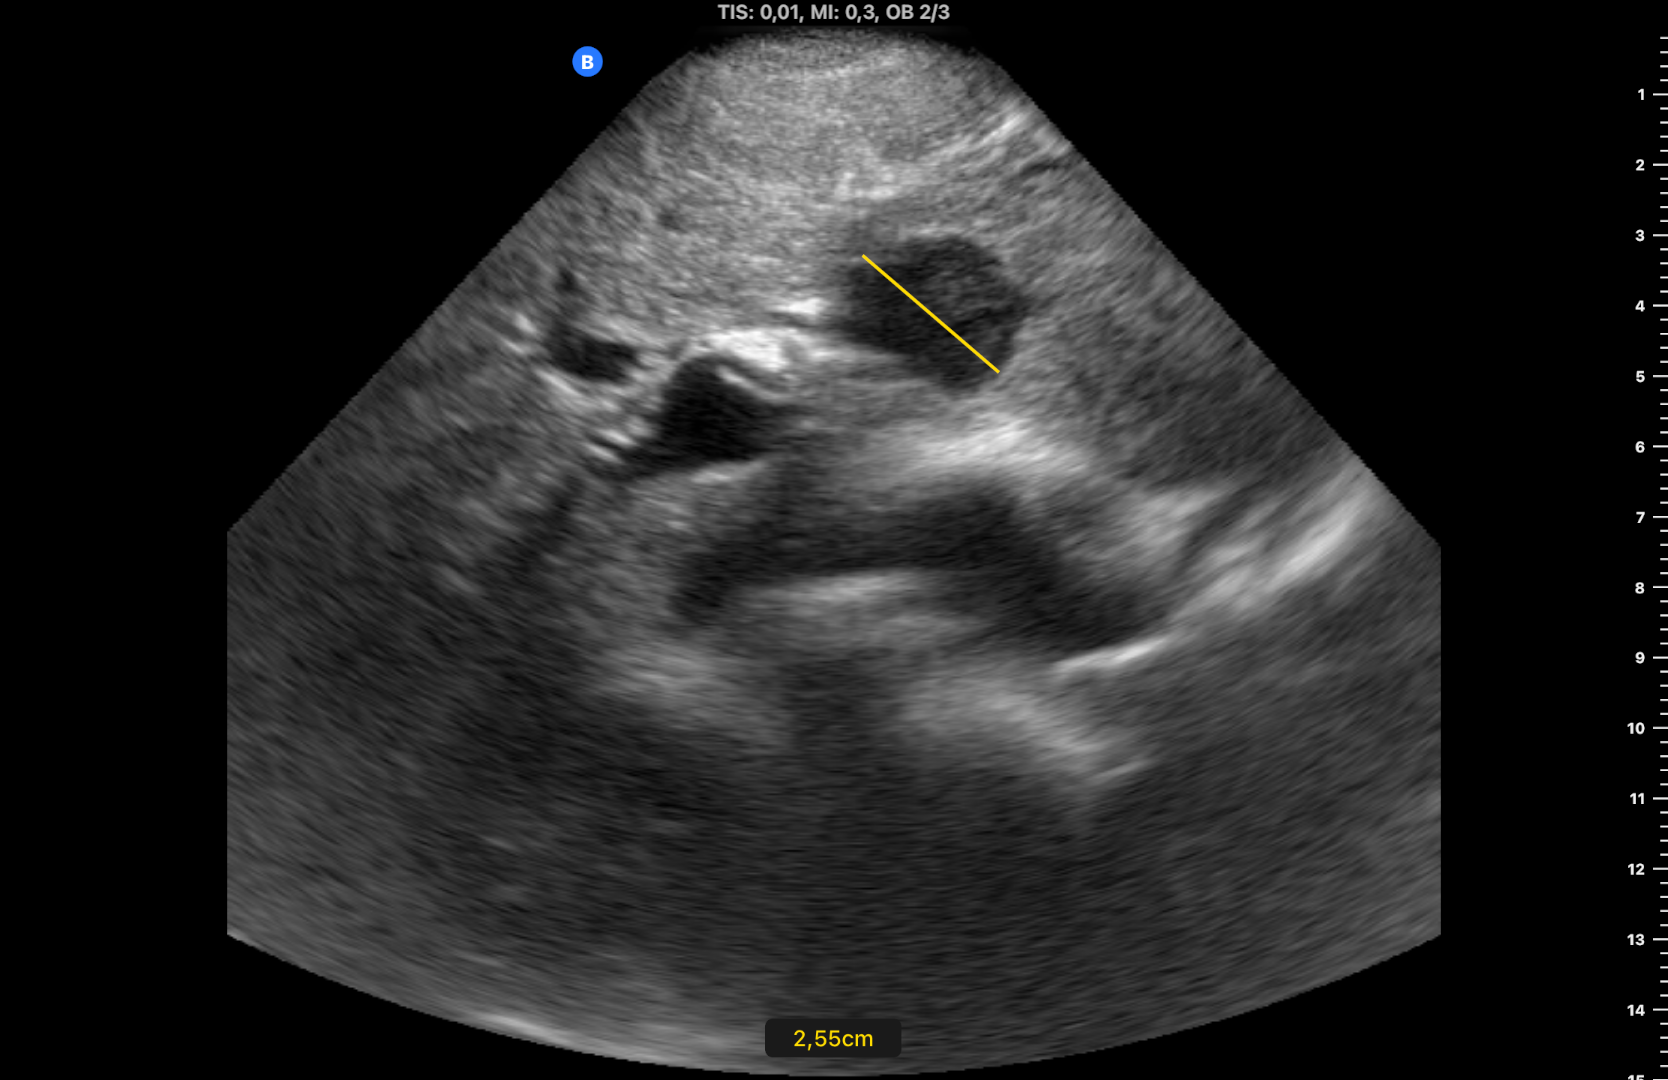

Se observan dos imágenes hipoecogénicas en el parénquima hepático, bien delimitadas, con alguna lobulación a nivel de segmento 3 y en lóbulo caudado de 2,5 y 1,2 cm de diámetro (figuras 1 y 2) y una porta de 13,1 mm de calibre. Se confirman los hallazgos con ecógrafo de consola (figura 3) (vídeos disponibles).

Seis meses después, al revisar la historia su médico advierte que el paciente olvidó su cita y vuelve a derivarlo tras realizar otra ecografía clínica, observando las mismas lesiones sin cambios (figura 4), lo que sugería benignidad. Finalmente se realiza TC: «lesión hipodensa de apariencia sólida en lóbulo caudado de 14 mm y lesión subcapsular de 9 mm en segmento VIII» y RM: «múltiples lesiones hepáticas benignas, la mayoría corresponden a angiomas hepáticos (los de mayor tamaño se localizan en los segmentos 1 y 3), otras se corresponden a pequeños quistes biliares subcentimétricos».